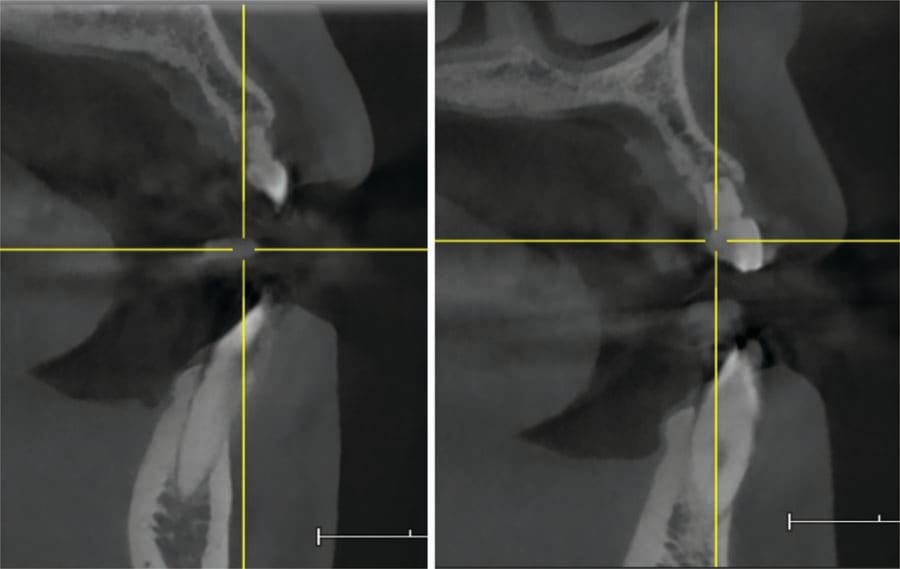

The oral surgeon, Dr. Defalco, saw the patient, and a CBCT was taken. Cross-sectional views at 6 and 11 noted a narrow ridge width due to a concavity at both sites related to lack of the permanent canines (Figure 5). Minimal roots were present for the deciduous canines (teeth C and I). Insufficient ridge width was present at either site to permit implant placement without site grafting to eliminate the facial ridge concavity. Block grafting of the sites at the time of extraction was recommended, and following site healing and graft conversion to the host ridges implants could be placed.